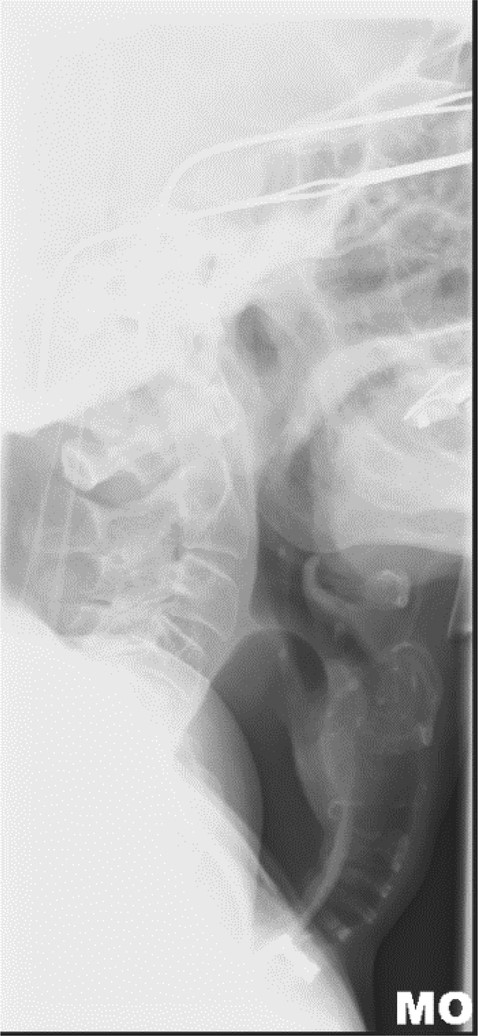

Lateral neck X-ray showing dilated oesophagus displacing trachea anteriorly.